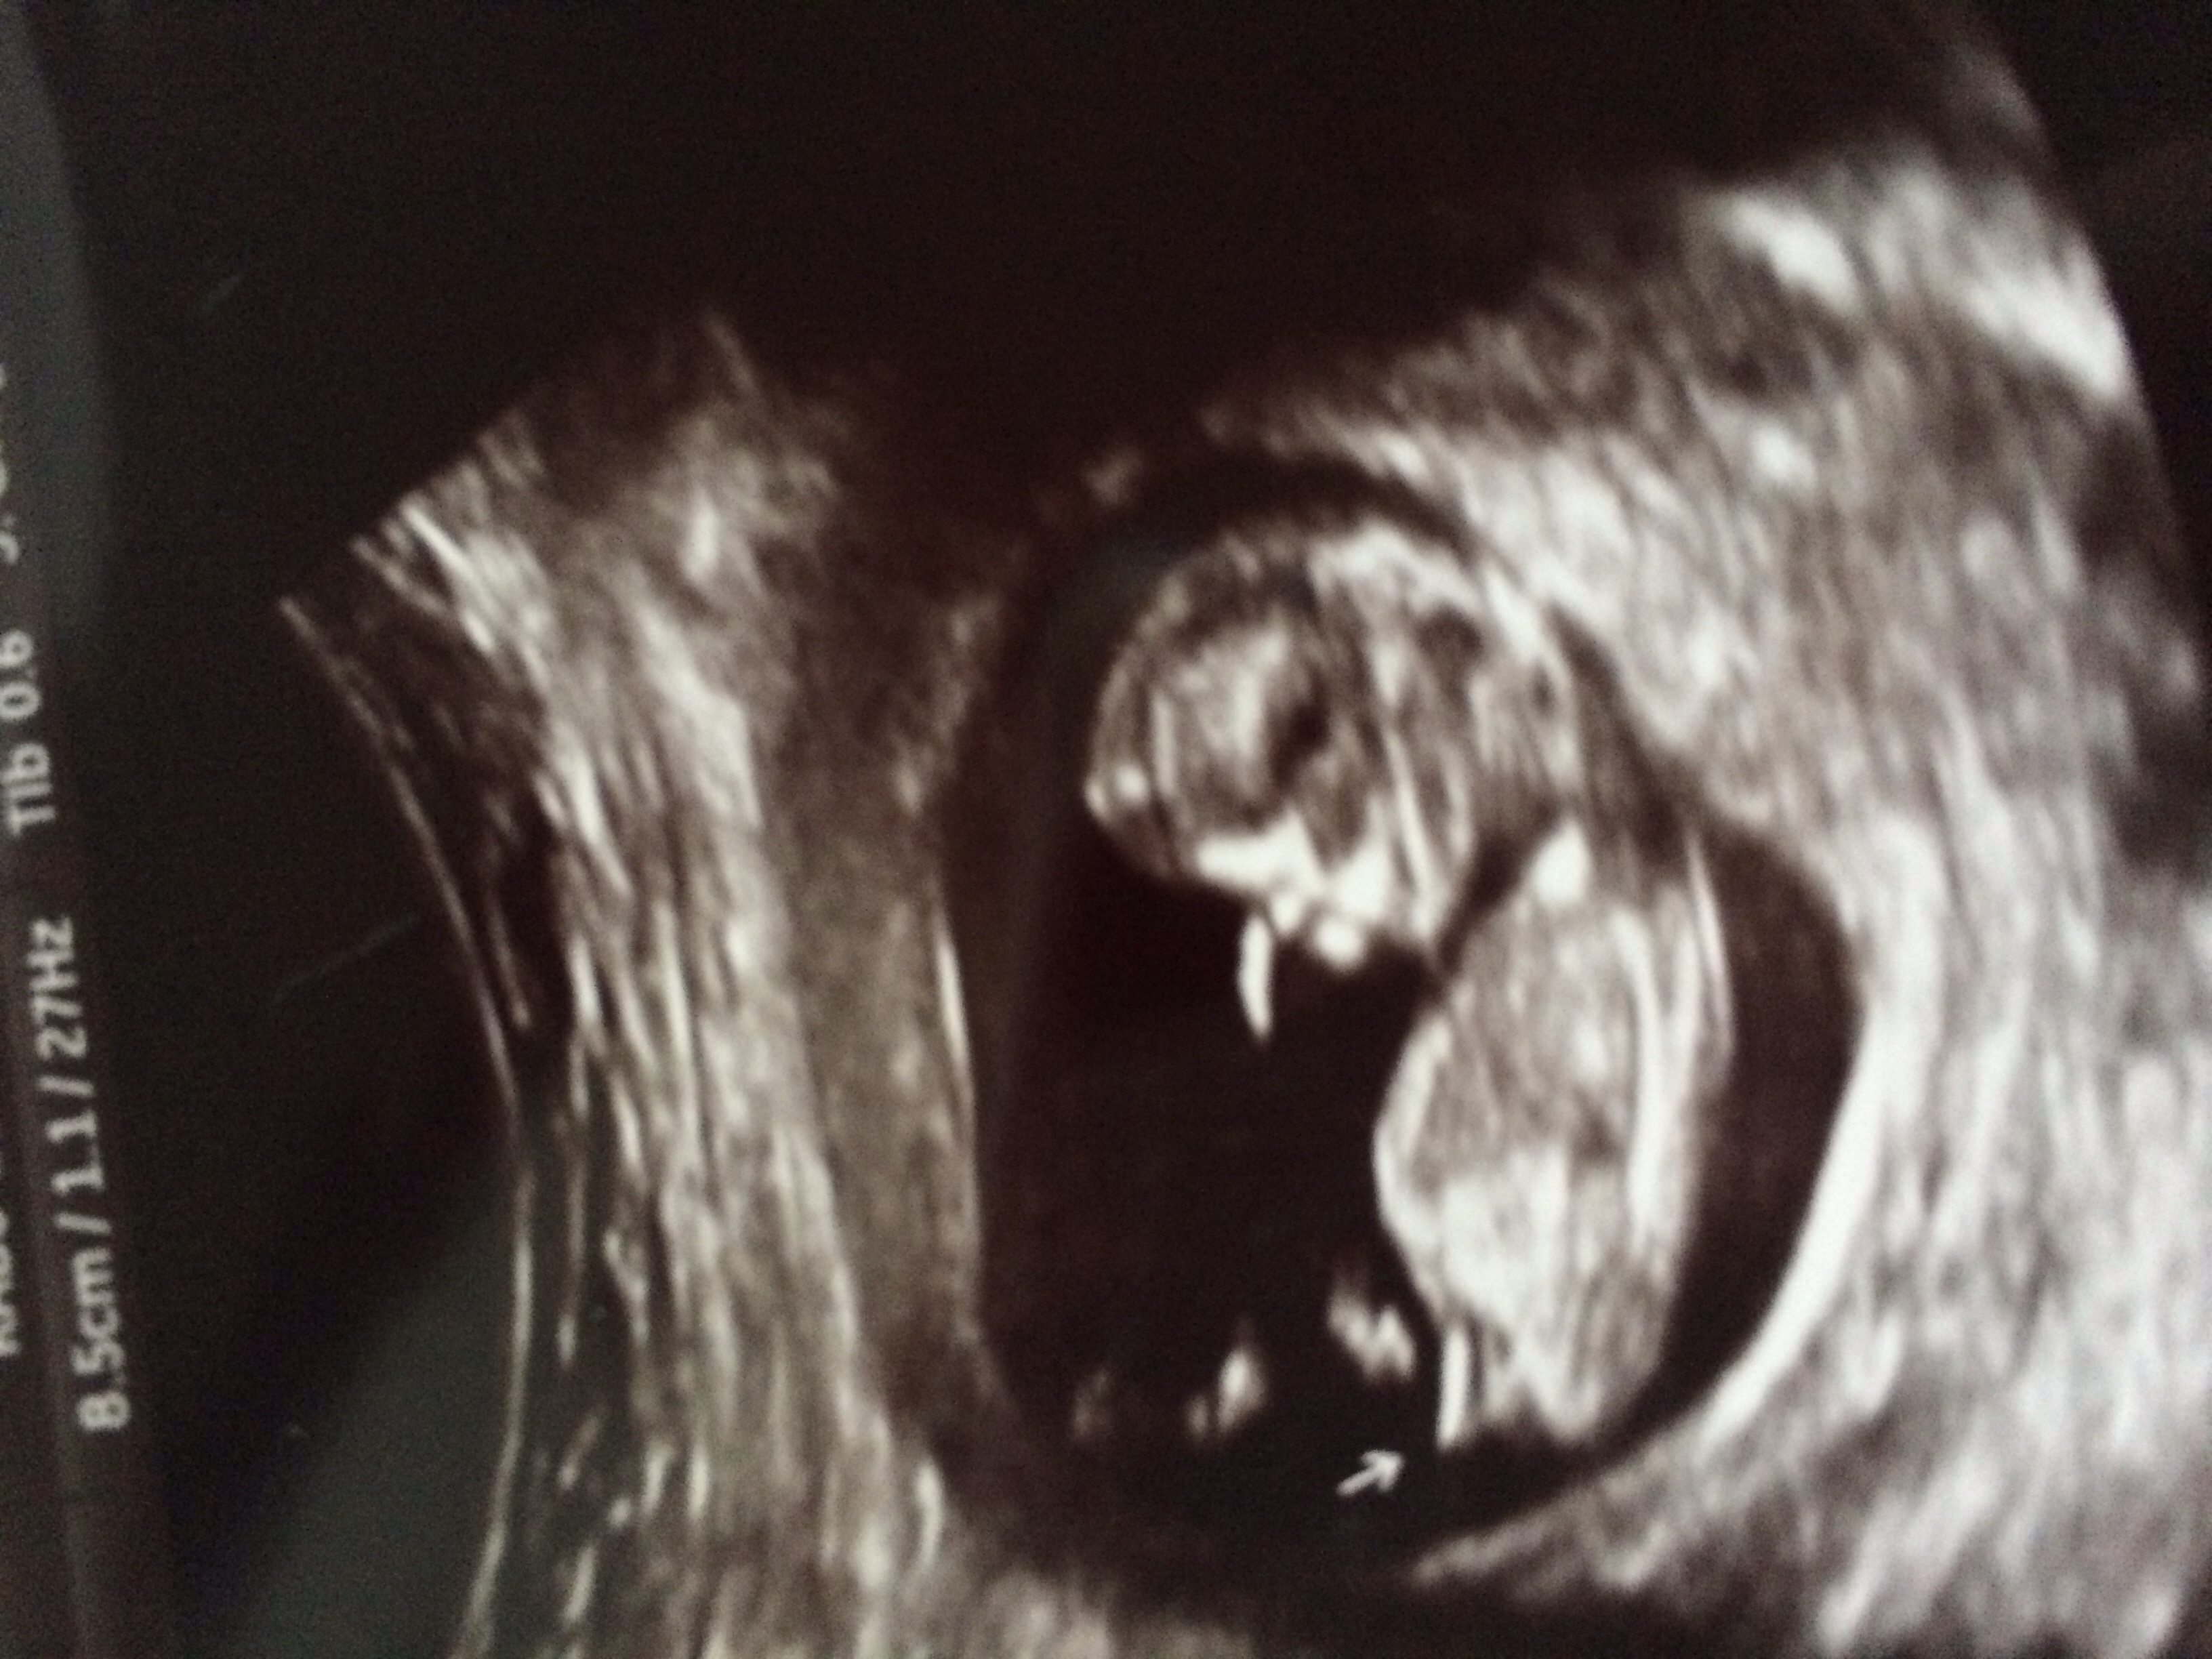

I already got 100% girl guess based off nub but wanted to see if anyone could look at skull or anything else to guess? This was taken in beginning week 12Attachment 16494Attachment 16494Attachment 16495